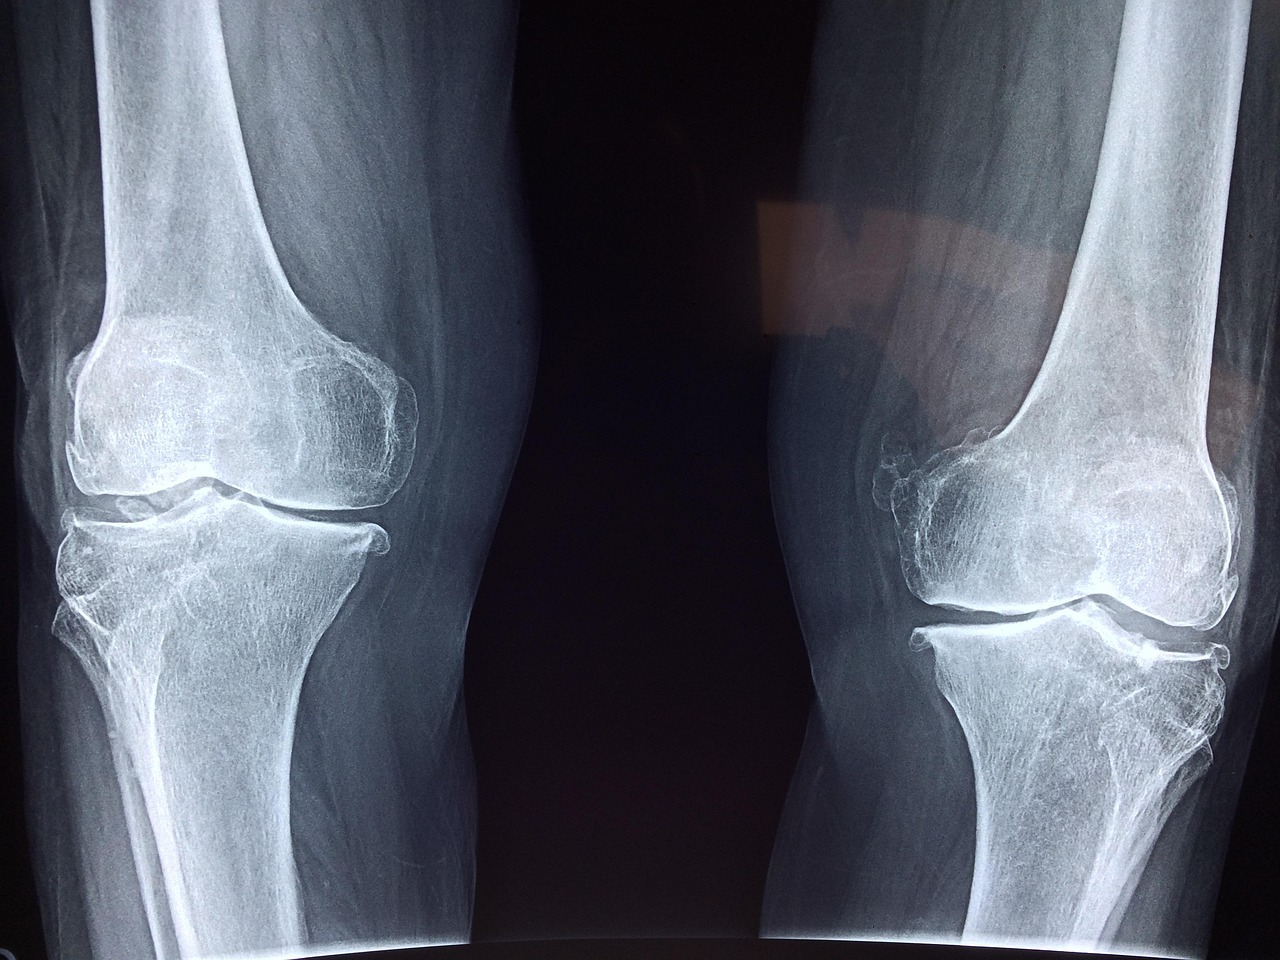

Cycling contributes positively to joint health primarily through its low-impact nature. Regular cycling helps fortify the muscles surrounding the joints, which can mitigate the risk of injury. Strengthened muscles provide better support to the joints, resulting in increased stability and decreased pain during various activities. Additionally, cycling increases synovial fluid production, which lubricates joints, allowing for smoother, pain-free movement. This is particularly beneficial for older adults and those with pre-existing joint conditions. Another significant benefit of cycling is the improved range of motion it promotes. As cyclists pedal, they engage in a fluid motion that helps maintain or improve flexibility in the legs, hips, and knees. By encouraging a full range of motion, cycling assists in combating stiffness and pain often associated with joint issues. Moreover, the cardiovascular workout obtained from cycling is beneficial for maintaining a healthy weight, which is crucial for reducing undue stress on the lower body joints. For anyone looking to enhance their joint health while enjoying physical activity, cycling is an excellent, holistic choice to consider incorporating into their routine.